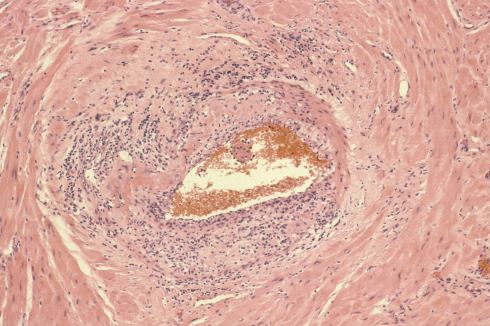

I regret not having explored and recorded more of the vascular anatomy in the uteri that I examined. The focus was on the diagnostic features of accreta, or possible causes of atony. One incidental observation that I could not explain in a uterus removed for placenta accreta was severe chronic inflammation in a deep myometrial artery in which a portion of the artery was necrotic suggesting trophoblastic remodeling (Figs 5a, 5b).

Fig 5a: The artery in the center is surrounded by large gravid myometrial myocytes. Its wall on the right is intact, but the left, top and bottom shows loss of medial smooth muscle, numerous inflammatory cells, and smudged eosinophilic material in the media. H&E 10x

Fig 5b: This image is a higher magnification of the above artery at the junction of intact and damaged media. The inflammatory cells appear to include neutrophils, lymphocytes and even plasma cells. H&E 40x